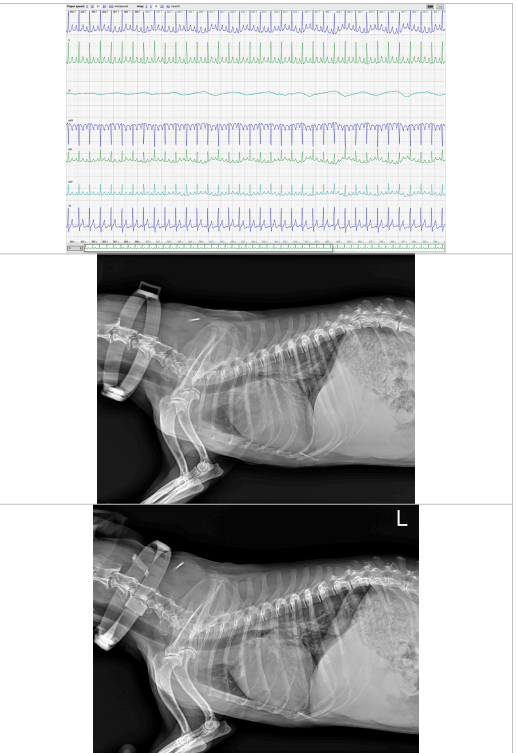

【心臟超音波】模板範例

這個是為我們會傳給-來美術德民掃心臟超音波的主人的報告 有要做心臟檢驗的毛孩主人們可以參考一下喔! 我們將會给您一份如下圖非常完整的報告.並且給予接下來的治療計畫及建議 無論之後是否持續在本院治療都能夠給您帶回去作紀錄,或是給其他醫師作為之前治療的一份參考